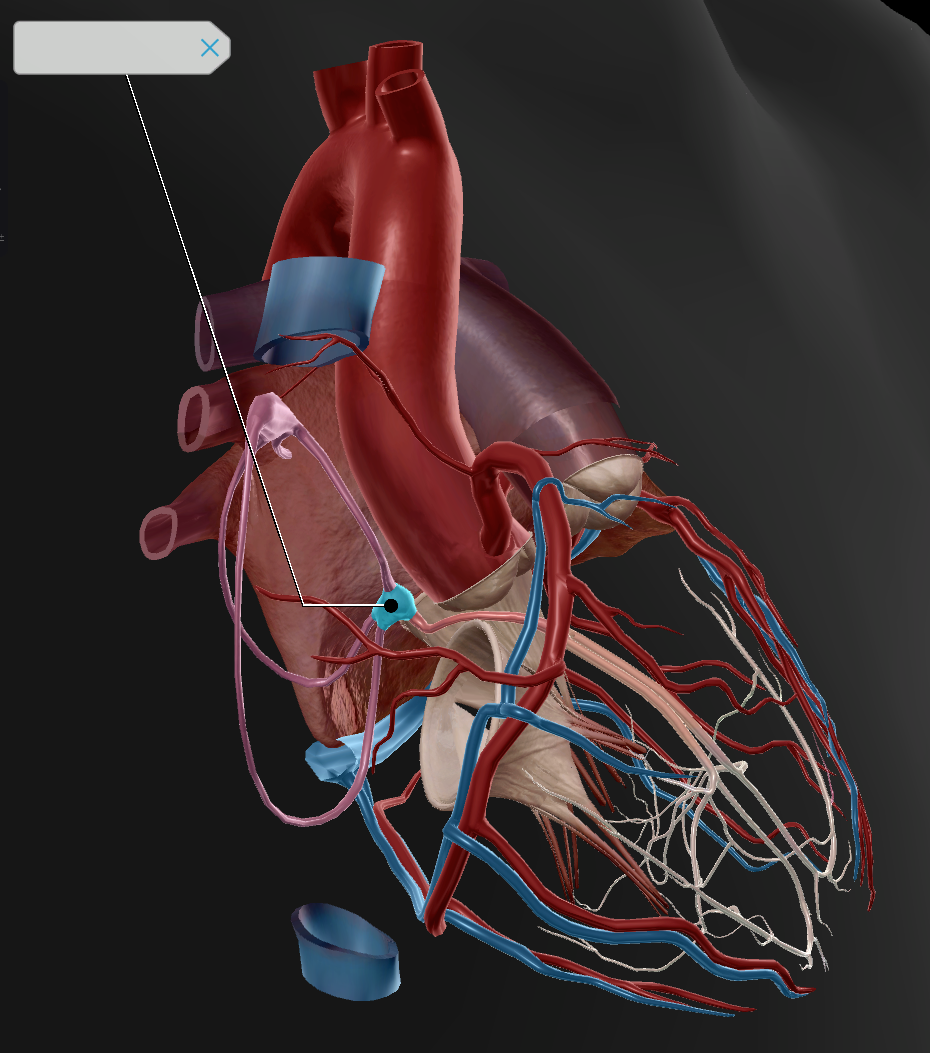

Anterior Interventricular Artery

Circumflex Branch

Coronary Artery

Middle Cardiac Vein

AV Node

SA Node

Bundle of His

Coronary Sinus

Anterior Interventricular Sulcus

Interatrial Septum

Coronary Sulcus

Small Cardiac Vein

Anterior Cardiac Vein

Coronary Veins

Marginal Branch

Circumflex Artery

Great Cardiac Vein